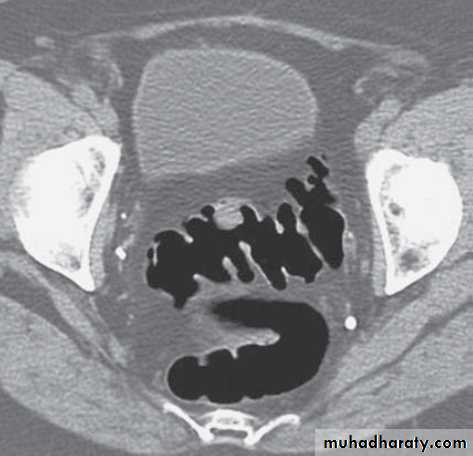

Colorectal carcinoma

• Colorectal carcinoma (CRC) is the second leading cause of cancer death in Western society.

• CRC may present clinically with large bowel obstruction, GIT bleeding, or less specifically with weight loss or anemia.

• A large percentage of CRC show locally invasive disease or distant metastases at the time of presentation.

• The vast majority of CRCs develop from small adenomatous polyps through a series of genetic mutations.

• The adenoma–carcinoma sequence is a slow process. On average, 5.5 years is required for large adenomas greater than 10 mm diameter to develop into CRC, with 10–15 years for small adenomas (<5 mm).

• Colonic polyps are very common; not all are adenomas and not all will develop cancer.

• Most polyps less than 5 mm are hyperplastic polyps or mucosal tags; these are not cancer precursors. Less than 1 per cent of adenomas up to 1 cm in diameter contain cancer, with cancer in small polyps (<5 mm) being extremely rare.

• CT of the abdomen is the imaging investigation of choice for detection of locally invasive disease, lymphadenopathy and distant metastases in patients with CRC.

• CT is unable to assess the depth of wall invasion or detect small metastases in non-enlarged lymph nodes. Therefore, CT is accurate for advanced disease though less so for earlier noninvasive disease.

• MRI and trans-rectal US (TRUS) are able to differentiate the layers of the rectal wall. These modalities are therefore able to assess accurately the depth of invasion of rectal tumor.